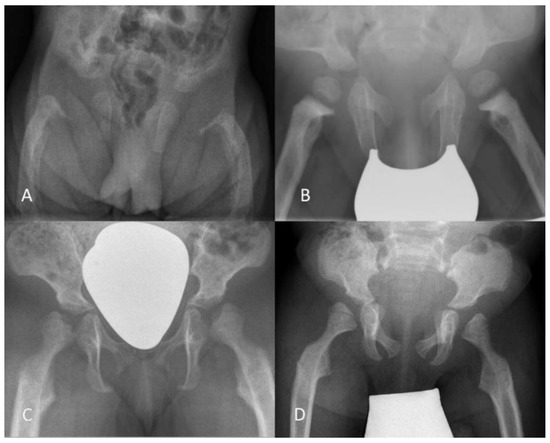

3.2.1. Radiography

3.2.3. Qualitative Assessment of Radiographs